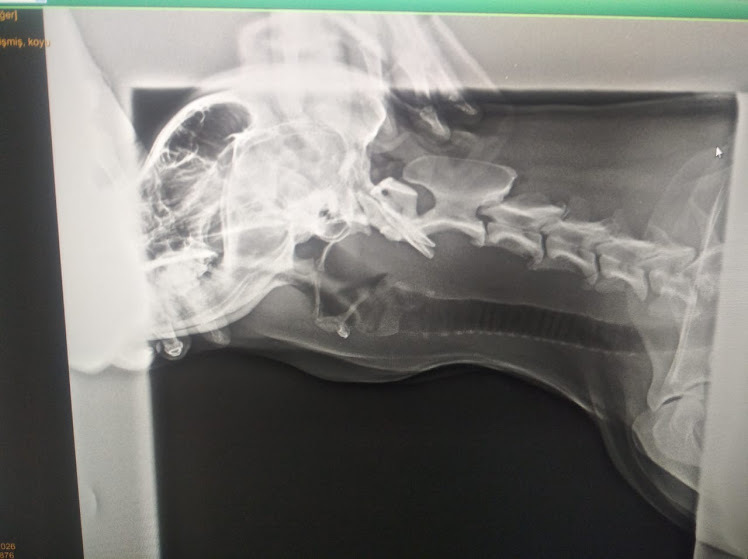

У собаки на шее обнаружилась опухоль. Рентген подтвердил, но врачи не знали происхождение опухоли. Может там в пищеводе застрял мячик, проглоченный псом, или плотное мясо, мешающее собаке глотать. Еще была версия опухоли после ангины, которой собака действительно недавно болела.

Выяснить причину утолщения можно в ходе операции, но врач сказал, что не уверен в благополучном исходе. Против операции выступили мы - хозяева. Доктор массировал опухоль рукой, наверное надеясь вытолкнуть в пасть собаки то, что может быть, застряло. Но псу стало больно и он вежливо отошел от врача, поскулив от боли.

Обследование - 10 манат, рентген - 25 манат. Про хирургическую операцию и спрашивать не стали.